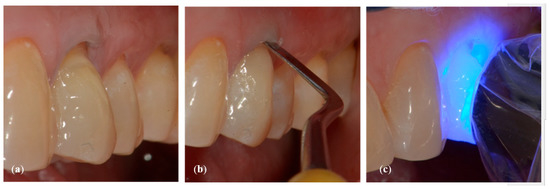

- Application of a thin layer of flowable composite (3M Filtek Supreme flowable, 3M Italia Srl,Via Norberto Bobbio, 21, 20096 Pioltello (MI) Italy) on the bottom of the cavity and of composite (3M Filtek Supreme XTE, 3M Italia Srl,Via Norberto Bobbio, 21, 20096 Pioltello (MI) Italy), on top and perimeter seal, by means of a layering procedure. The composite was applied in horizontal excess following the principles of the BOPT technique, trying to emphasize the cervical convexity. The polymerization phases were performed using the KERR (KERR ITALIA SRL,Via Passanti 332 84018 Scafati, Italia) 800 Watt lamp for 20″ for each layer [23] (Figure 6a–c).